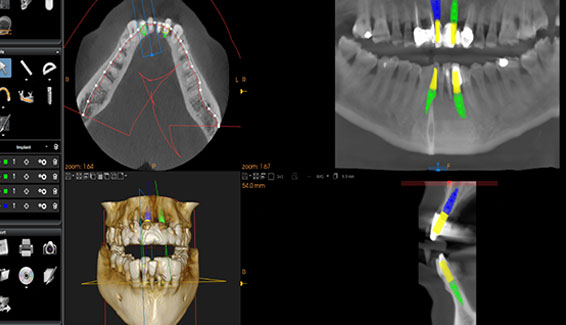

ADVANCED TECHNOLOGY

To Ensure our patients get the best outcomes we use advanced 3D technology for:

Examination, Treatment Plan, Design and Build

Treatment Planning

Sophisticated digital technology is used to carryout treatment planning to achieve excellent clinical outcomes. Apart from the high-definition photographs Carestream Software... Read More>>>